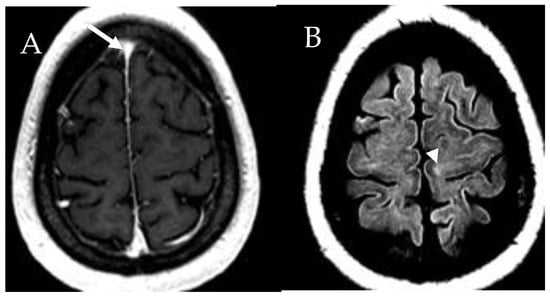

6.6. Central Nervous System